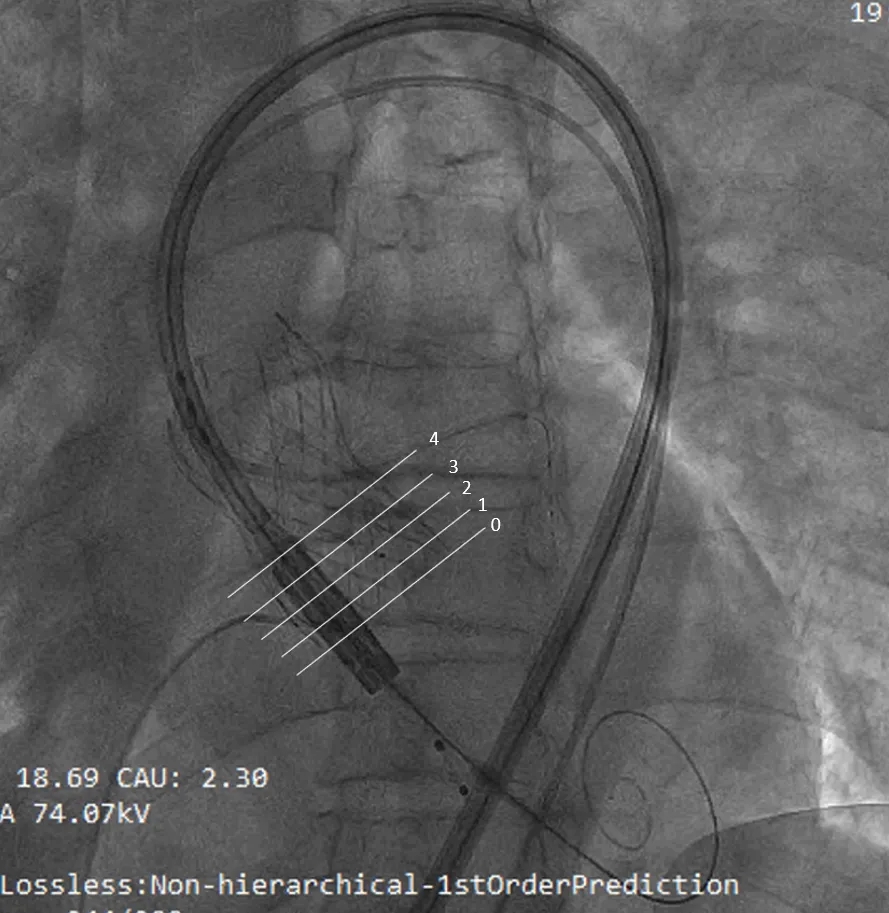

术前讨论:患者77岁老年男性,3年前行TAVR术,此次再发主动脉瓣关闭不全,经评估排除感染,考虑主动脉瓣生物瓣毁损,患者心衰重,消瘦、虚弱,经多学科讨论,TAVR in TAVR手术指征明确,考虑行TAVR in TAVR治疗,术前评估瓣架内径:瓣环26.6,LVOT 26.6,瓣架位于瓣环以下:5(无窦)-13(左窦)mm,左侧冠脉高度12.1,右侧13.4,左冠VTC5.3mm VT-STJ:0mm,右冠VTC4.4mm VT-STJ0mm, 主动脉弓部角度可,存在钙化,双侧髂股动脉内径可,右侧股动脉分叉位于股骨头平面中部 左侧股动脉分叉位于股骨头下缘中部,建议左侧入路,拟植入29号瓣膜,因患者冠脉风险大,需控制瓣膜植入深度,拟控制S3上缘位于启明第3-4个交接点处,同时需关注冠脉(Guidzilla预置保护)。

左冠保护下THV过弓及跨瓣

S3定位及植入

(1)TAVR in TAVR中需重点评估冠脉风险,相较于自体瓣膜评估,瓣中瓣植入过程中,需重点关注几个指标(图6):coronary risk plane(CRP),New-skirt Plane(NSP),VTA:VTC,VTAoS,VTSTJ。主要原因在于人工瓣膜将会形成新的封堵平面,术前评估中需重点关注。

(2)需熟悉人工瓣膜挂瓣高度,本例患者植入启明瓣膜,其封堵挂瓣高度为Node 3至Node 6。

(3)球扩瓣不同植入深度,将影响第一个瓣膜封堵区域(图8),本例患者在不影响二尖瓣前叶情况下,采用较深的植入深度:node 3-4之间(图9),最大限度规避冠脉堵塞风险,术后结果满意。